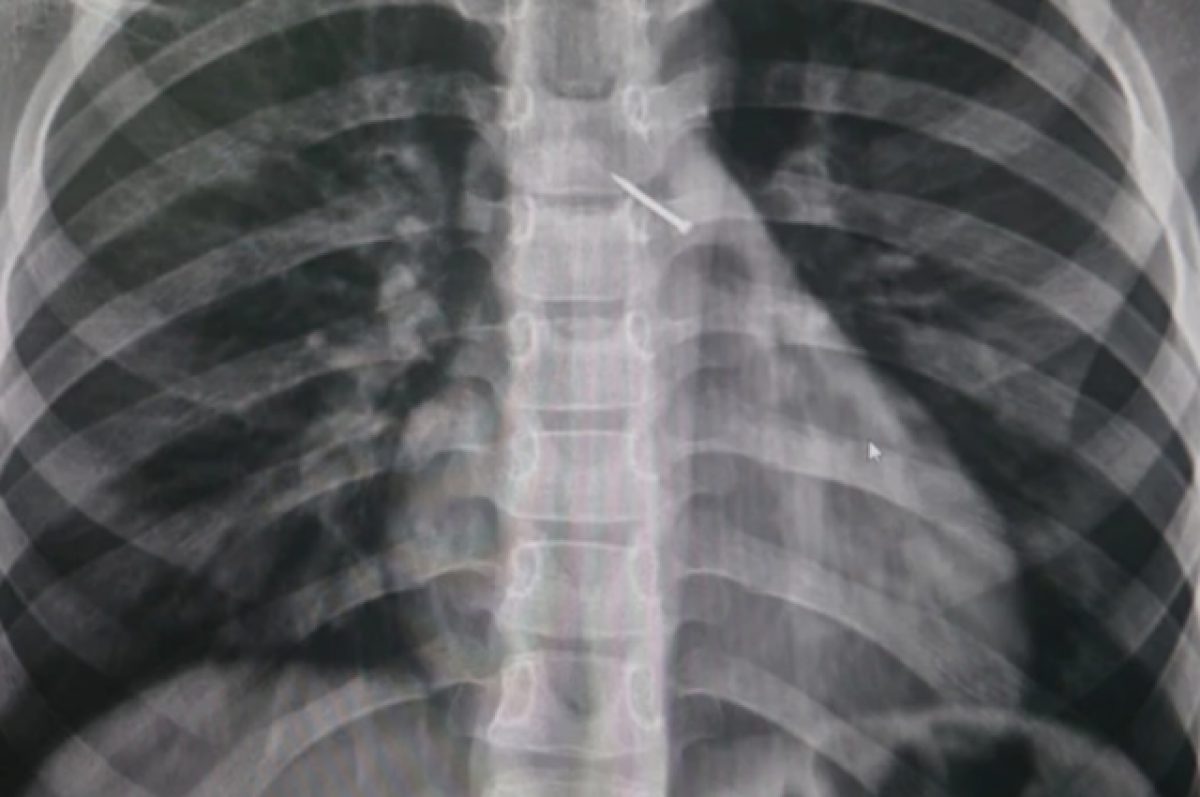

В Новосибирске 9-летний мальчик во время игры на улице вдохнул канцелярскую кнопку. Его родители обратились в больницу. Ребенок чувствовал боль в груди и не мог нормально вдохнуть. Об этом сообщили в региональном Министерстве здравоохранения. Врачи провели обследование, которое показало, что кнопка попала в бронхи школьника. Она уперлась в одну из стенок и вызвала локальное воспаление. Заведующая эндоскопическим отделением Ольга Ахалкалакелова отметила, что медики успешно достали предмет с помощью эндоскопических зажимов. Всего школьник провел в больнице четыре дня. Он находился под наблюдением врачей. Мальчику потребовалась ингаляционная терапия. Сейчас с ребенком все в порядке. По информации Минздрава, за неделю в больницы поступает несколько обращений с инородными предметами в желудочно-кишечном тракте и бронхах, у детей — в носовых и слуховых проходах. Родителей просят быть предельно внимательными и не допускать игры с мелкими предметами.

Об этом сообщили в региональном Министерстве здравоохранения. Врачи провели обследование, которое показало, что кнопка попала в бронхи школьника. Она уперлась в одну из стенок и вызвала локальное воспаление.